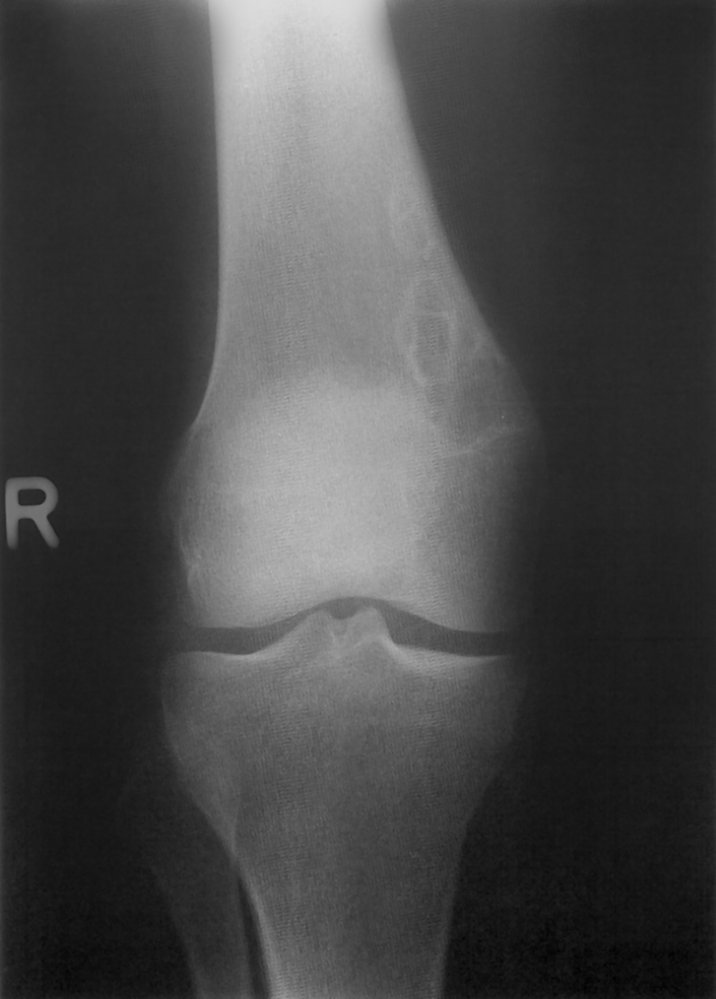

• Description: benign but locally aggressive tumor composed of giant cells that arise from the bone marrow [1]

• Epidemiology: peak incidence between 20 and 40 years

• Clinical features

• Found in the epiphysis or metaphysis of long bones (especially knee region)

• Pathological fractures

• Local pain and swelling

• Limited range of motion

• Diagnostics

• X-ray: multicystic osteolytic lesions (soap-bubble appearance)

• Histopathology

• Mononuclear, RANKL-expressing cells (neoplastic)

• Multinucleated giant cells (are reactive and resemble osteoclasts)

• Treatment: curettage and bone grafting or en-bloc resection to minimize recurrence rate

• Prognosis: risk of malignant degeneration increases with age; may spread to the lungs